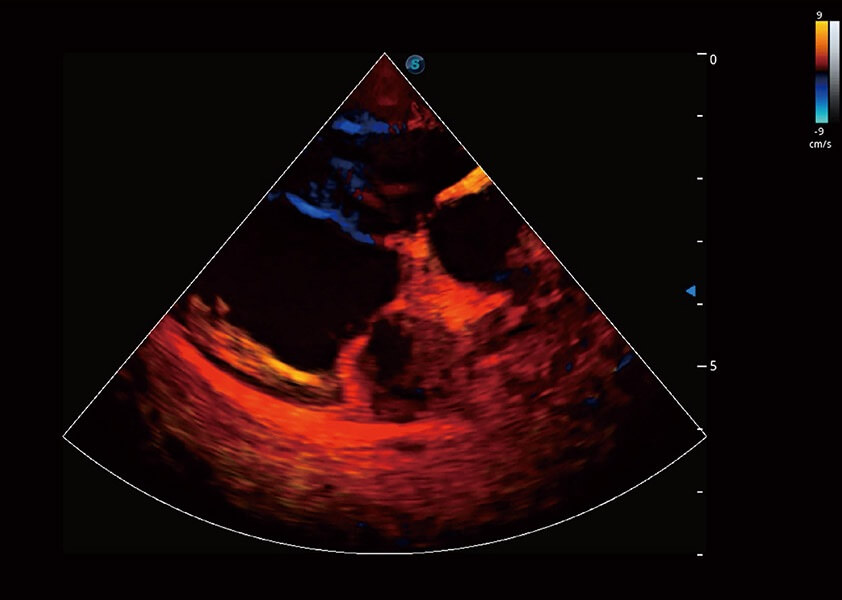

ProPet 60 作为一款高端台式动物超声设备,为动物医生的日常诊断提供了一系列贴合动物临床需求、解决临床实际问题的高级成像功能。凭借全系列高清探头,满足医生对腹部、心脏、生殖、浅表、肌骨等成像的所有需求,切实帮助您提升检查效率,提高诊断信心。

动物是人类最亲密的朋友和最值得信赖的伙伴。16877太阳集团也一直致力于探索动物专用的超声影像解决方案。 全新推出的ProPet系列,是16877太阳集团在动物超声影像智能化、专业化、精准化的一次跨越式革新。动物不能用言语来表述自己的不适,通过超声影像,ProPet系列搭建了动物医生与不同物种沟通的“桥梁”,为动物医生注入了“治愈之力”。